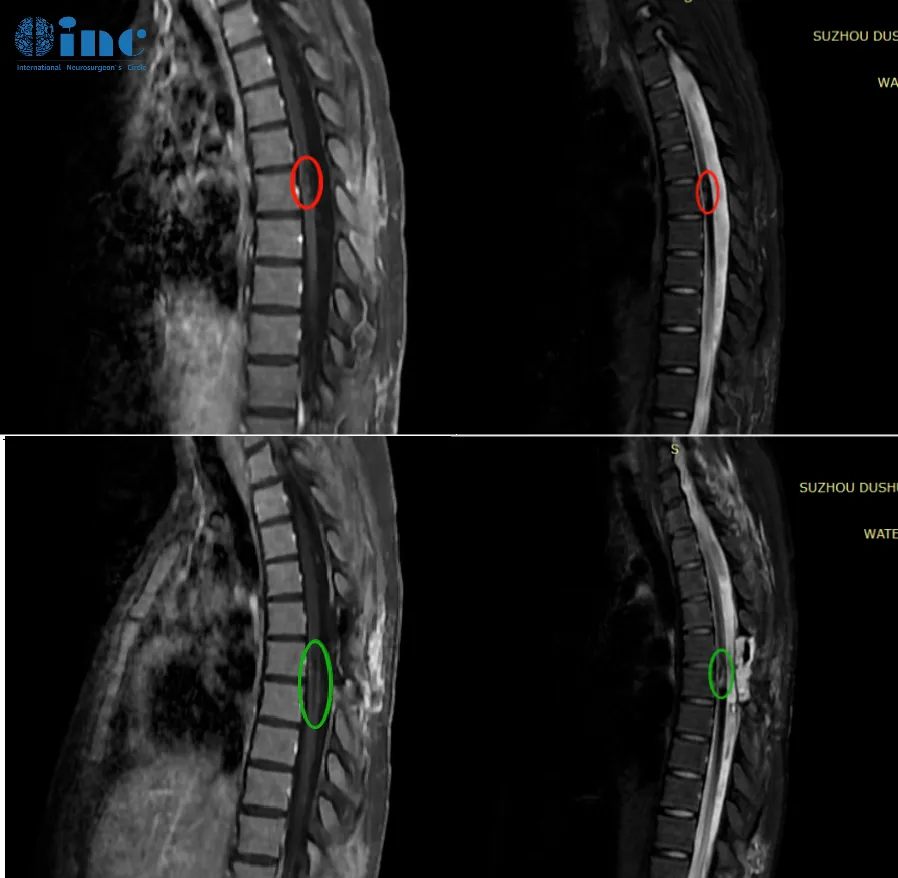

28岁的潇潇2017年左右开始出现肩部至腰部疼痛,刚工作的她以为是工作疲劳导致的,并未引起特别重视。然而2021年,潇潇肩部后侧疼痛加剧,于当地医院行磁共振检查,提示髓内占位性病变,保守治疗无效。2022年10月磁共振提示8*12*19mm。肿瘤持续进展,年轻的潇潇不愿意继续坐以待毙,在病友的下,她了解到——INC德国巴特朗菲教授。

2022年12月4日,苏州独墅湖医院,潇潇的手术顺利进行,巴教授顺利全切潇潇脊髓髓内的肿瘤,术后一天ICU查房,潇潇已经清醒,意识清楚,四肢能够正常活动。

术后两个多月,潇潇随访视频中她已经可以自如行走活动、抓握物体上举正常……看起来几乎和常人无异。